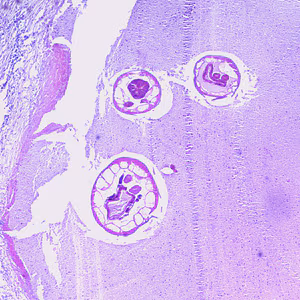

Oesophagostomum spp. in tissue specimens.

Diagnosis is difficult during routine ova and parasite (O&P) examinations of stool, due to the similarity of Oesophagostomum eggs to the eggs of Necator and Ancylostoma. Eggs tend to be shed in greater numbers during cases of oesophagostomiasis than hookworm infection, however. Finding an intact worm during surgery or in a biopsy specimen can provide a definitive diagnosis.